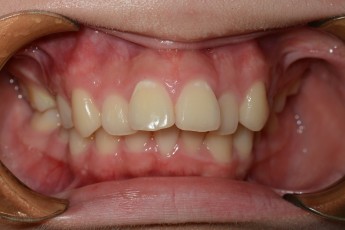

BEFORE & AFTER

- 덧니교정

- 매복치교정